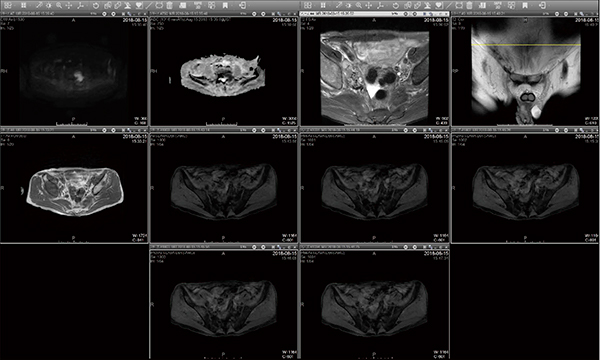

一方,1回の検査で複数のシーケンスを撮像するMRIの読影では,従来,検査によってはシーケンスの撮像順が変わり,読影時モニタ上に表示される画像の順番も異なってしまっていたが,SRPを用いることで画像診断医があらかじめ設定した画像表示レイアウトへ自動的に並べ替えることが可能である。例えば,前立腺のMRI検査では,通常の表示画面の設定を変え,上部に拡散強調画像,ADC,T2強調画像を,下部にT1強調画像,造影MR画像を配置するレイアウトにしている(図3)。撮像の順番に関係なく,画像診断医の好みに応じて最適なレイアウトを作成し,ワークフローの効率化に役立てている。

図3 SRPを用いた前立腺のMRI検査での画像表示レイアウト